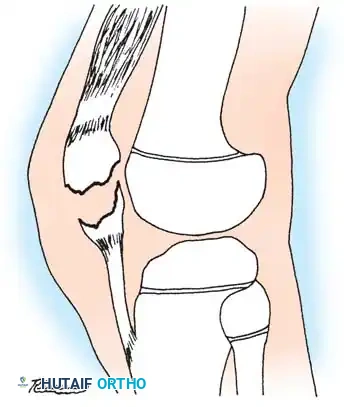

The "sleeve" fracture is a pathognomonic pediatric injury that demands high clinical vigilance. It involves the avulsion of a large cartilaginous envelope (the "sleeve") from the main body of the patella, typically at the distal pole, carrying with it the patellar tendon insertion.

Radiographically, this injury is notoriously deceptive. Because the avulsed fragment is predominantly unossified cartilage, the standard lateral radiograph may only reveal a minute "fleck" of bone. This falsely benign appearance frequently leads to missed diagnoses.

If left untreated, the cartilaginous sleeve continues to generate bone, healing in a malaligned and elongated position. This results in severe patella alta, extensor lag, and an abnormally elongated patellar mechanism. If the initial injury occurred in conjunction with a patellar dislocation, this resultant elongation exacerbates patellofemoral instability, leading to chronic, recurrent dislocations.

Surgical Warning: When a pediatric patient presents with an inability to perform a straight leg raise, a palpable infrapatellar defect, and a high-riding patella, a sleeve fracture must be assumed regardless of how benign the radiograph appears. Magnetic Resonance Imaging (MRI) is the gold standard for delineating the true extent of the cartilaginous avulsion.